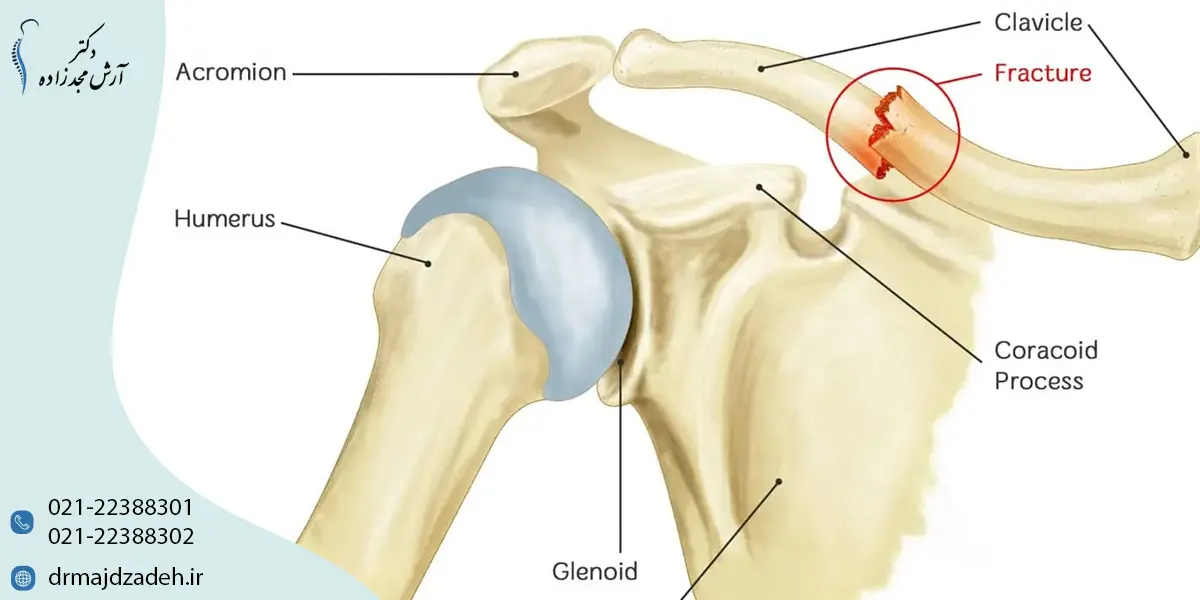

شکستگی ترقوه یا شکستگی استخوان ترقوه یکی از شایعترین آسیبهای اسکلتی در ناحیه شانه است که میتواند در اثر ضربه، زمینخوردن یا تصادف ایجاد شود. این نوع شکستگی اگرچه در بسیاری از موارد قابل درمان است، اما در صورت بیتوجهی یا درمان نادرست میتواند باعث درد مزمن، کاهش عملکرد شانه و محدودیت حرکتی طولانیمدت شود. آشنایی با علائم، روشهای تشخیص و درمان شکستگی ترقوه نقش مهمی در بهبود کامل و جلوگیری از عوارض دارد.

استخوان ترقوه یکی از اجزای اصلی کمربند شانهای است که بازو را به تنه متصل میکند و نقش مهمی در پایداری و حرکت شانه دارد. شکستگی ترقوه زمانی اتفاق میافتد که این استخوان در اثر نیروی مستقیم یا غیرمستقیم دچار ترک یا شکست کامل شود. در چنین شرایطی، انتخاب رویکرد صحیح برای درمان کتف و شانه درد اهمیت بالایی دارد، زیرا درمان ناقص یا تأخیری میتواند منجر به کاهش دامنه حرکتی، درد مزمن و اختلال در عملکرد شانه شود.

شکستگی ترقوه از نظر محل آسیب به چند نوع تقسیم میشود. شناخت نوع شکستگی به پزشک کمک میکند تا بهترین روش درمان را انتخاب کند. - شکستگی میانی ترقوه

این نوع شایعترین نوع شکستگی ترقوه است و معمولاً در بخش وسط استخوان رخ میدهد. اغلب موارد با درمان غیرجراحی بهبود مییابد. - شکستگی انتهایی نزدیک شانه

این شکستگی در نزدیکی مفصل شانه ایجاد میشود و ممکن است باعث ناپایداری شانه شود. - شکستگی نزدیک جناغ

این نوع کمتر شایع است و در محل اتصال ترقوه به جناغ رخ میدهد و نیاز به بررسی دقیقتری دارد.